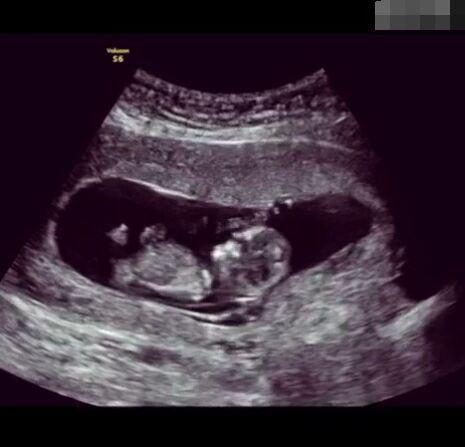

懷孕后,寶寶的性別一直是全家人的重點(diǎn)關(guān)注對(duì)象。而男女性別的差異,在基因?qū)用骟w現(xiàn)在第二十三對(duì)染色體上,如果是XY則是男孩,XX則是女孩,這都是由那枚與卵子結(jié)合的精子來決定。

那些做了B超檢查確定胎兒男女,生下來后發(fā)現(xiàn)不對(duì)的,多半是因?yàn)樵贐超檢查時(shí)寶寶太調(diào)皮,以致影響了檢查準(zhǔn)確性。就比如說,有的女寶寶在媽媽肚子里玩自己的臍帶,把臍帶夾到了兩腿中間,B超就有一定幾率拍出來好像是男寶寶的特征,導(dǎo)致被誤認(rèn)為是男孩子。還有些男寶寶過分害羞,在做B超時(shí)雙腿緊緊并攏,醫(yī)生也很難判斷男女,只好大致猜測是女孩,就又造成了誤會(huì)。因此,B超亦不是萬能的。